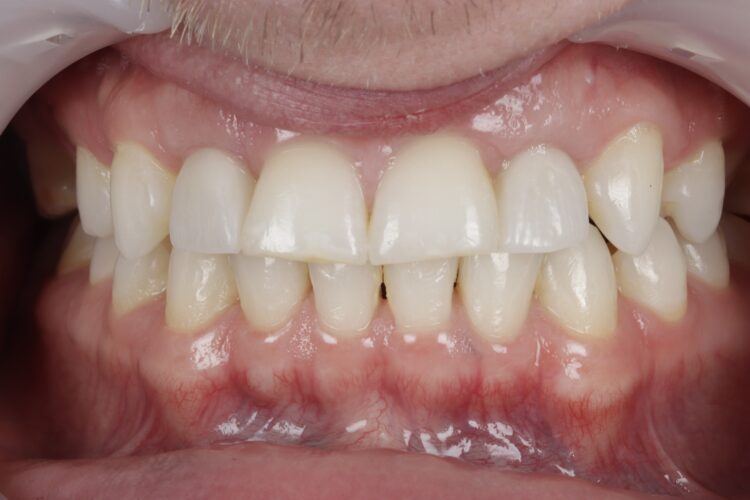

Case outcome

Both the patient and I were very happy with the outcome in this case. Given the patient’s reluctance towards excessive treatment, he was not willing to undergo any further procedures such as composite edge bonding or veneers, which could have enhanced the aesthetic result. However, he was more than satisfied with the replacement of his missing lateral incisors, and while he understands that more implants will be needed in the future when the remaining deciduous teeth are lost, he was happy to postpone that treatment for now.

This case presentation shows a real-life result of the kind of treatment we deliver every day in our clinic. It also demonstrates how a guided workflow allows us to place implants exactly as planned, making the process easier and more efficient.